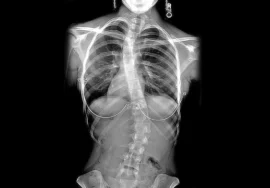

تم تسجيل حالة لفتاة عمرها 14 عامًا:

- كانت تعاني من مرض قلب خلقي منذ الصغر

- خضعت لعملية قلب مفتوح في عمر سنة

- ظهرت لديها علامات اعوجاج العمود الفقري في عمر 12 سنة

- بدأ الاعوجاج يتطور بسرعة

عند عمر 13 سنة:

- وصلت زاوية الاعوجاج إلى 46 درجة

- ظهرت أعراض نزيف من الفم

ما السبب؟

بسبب دوران الفقرات، حدث ضغط على الأوردة الرئوية، مما أدى إلى ارتفاع الضغط داخلها وظهور النزيف.